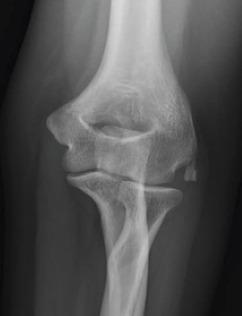

A 39-year-old female (right hand dominant) presented with the left elbow pain for the past 1 year. The diagnosis was achieved by radiography and confirmed by histopathology. Her pain did not respond to conservative treatment of analgesics, physiotherapy, and elbow support and a local steroid injection. She, therefore, underwent surgical exploration of the elbow, under general anesthesia. There was white-colored paste like a collection within the common extensor tendon origin, with dystrophic calcification of the tendon. The histology of the excised tissue revealed focal nodular aggregates of plump fibroblasts and osteoclastic giant cells around microcalcific foci. Large areas of fibrosis and calcific nodular deposits seen suggestive of calcific tendonitis.

一名39岁女性(右手为优势手),过去1年出现左肘疼痛。通过X线摄影确诊,并经组织病理学证实。她的疼痛对镇痛药、物理治疗、肘部支撑以及局部类固醇注射等保守治疗均无反应。因此,她在全身麻醉下接受了肘部手术探查。在伸肌总腱起点处有白色膏状物质聚集,肌腱存在营养不良性钙化。切除组织的组织学检查显示,微钙化灶周围有丰满的成纤维细胞和破骨巨细胞形成的局灶性结节状聚集。可见大片纤维化和钙化结节沉积,提示钙化性肌腱炎。